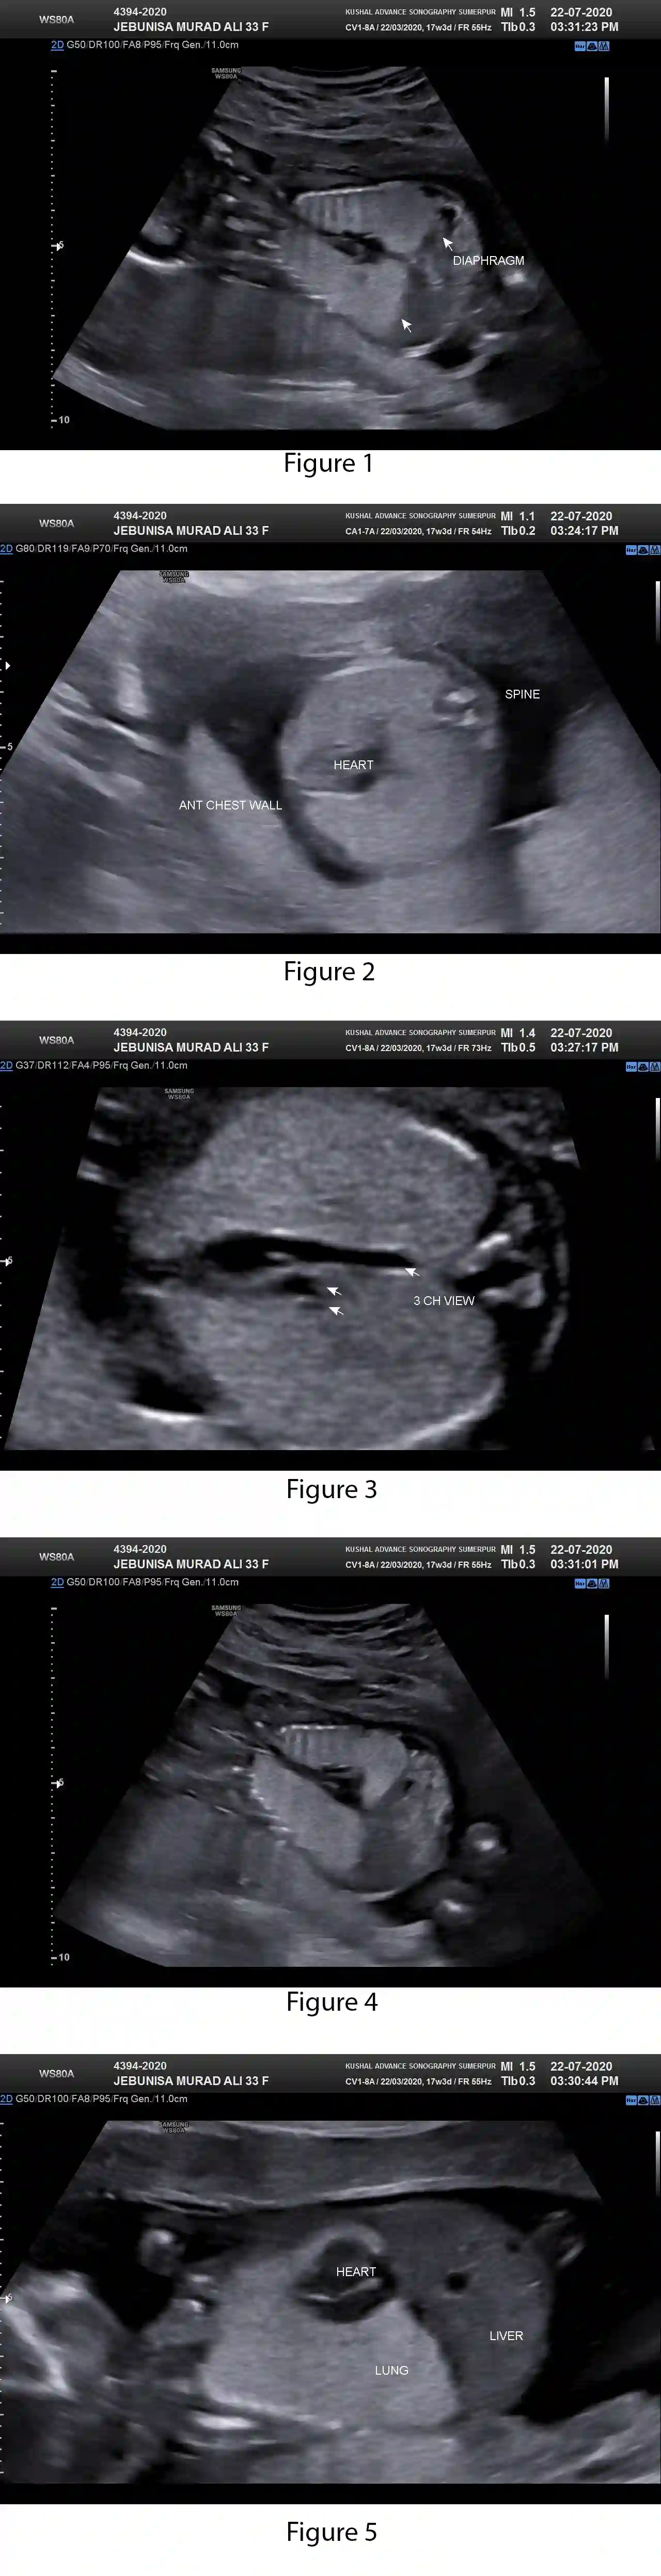

CHAOS, or Congenital High Airway Obstruction Syndrome.

Ultrasound features become evident ≥16 weeks’ gestation. The lungs are massively enlarged and hyperechogenic resulting in compression of the heart and development of ascites. The bronchial tree is dilated and the diaphragm inverted.